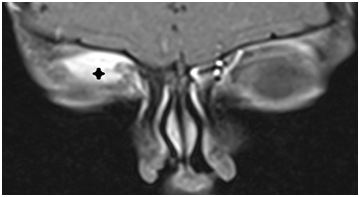

Figure 2a T1 axial MRI of the mass.

Figure 2b T1 coronar MRI with contrast of the mass.

Orbital MRI revealed a well-circumscribed mass lesion which is located extraconal, superior part of right orbit and behind the medial canthus, isointense with respect to brain parenchym on T1 and T2A, showed diffuse homogeneous contrast enhancement after intravenous injection of contrast. Lesion’s approximate size was 22x16x10 mm and pushing the eyeball and superior rectus muscle inferiorly. The mass caused to erosion in frontal bone. WBC: 17.690/dL, RBC: RBC: 1.55K/dL, Hgb: 4.6g/dL, Htc: 14g/L, Plt: 49K/dL were in complete blood account. Lactate dehydrogenase was 831U/L in biochemical examination. Peripheral blood showed an increased total leucocyte count (17,000cells/mm3). Her differential leucocyte count revealed 5% neutrophils, 12% lymphocytes, 2% eosinophils, 2% monocytes, 79% myeloblasts and immature myeloid precursors which included promyelocytes, myelocytes and metamyelocytes. Patient was t (8;21) positive and the subtype was AML M2. The bone marrow aspirate showed hyper cellular marrow smears with replacement of haemopoietic cells by blasts and blasts were Sudan Black B positive. Patient referred to paediatric haematology clinic and treated with standart cytarabine and anthracycline based chemotherapy protocole and re-evaluated at the end of the 2nd week of the treatment. Blasts were decreased to 15% and proptosis disappeared in examination. And the blasts decreased below to 5% at the end of 4th week and the choloma disappeared in the orbital MRI.